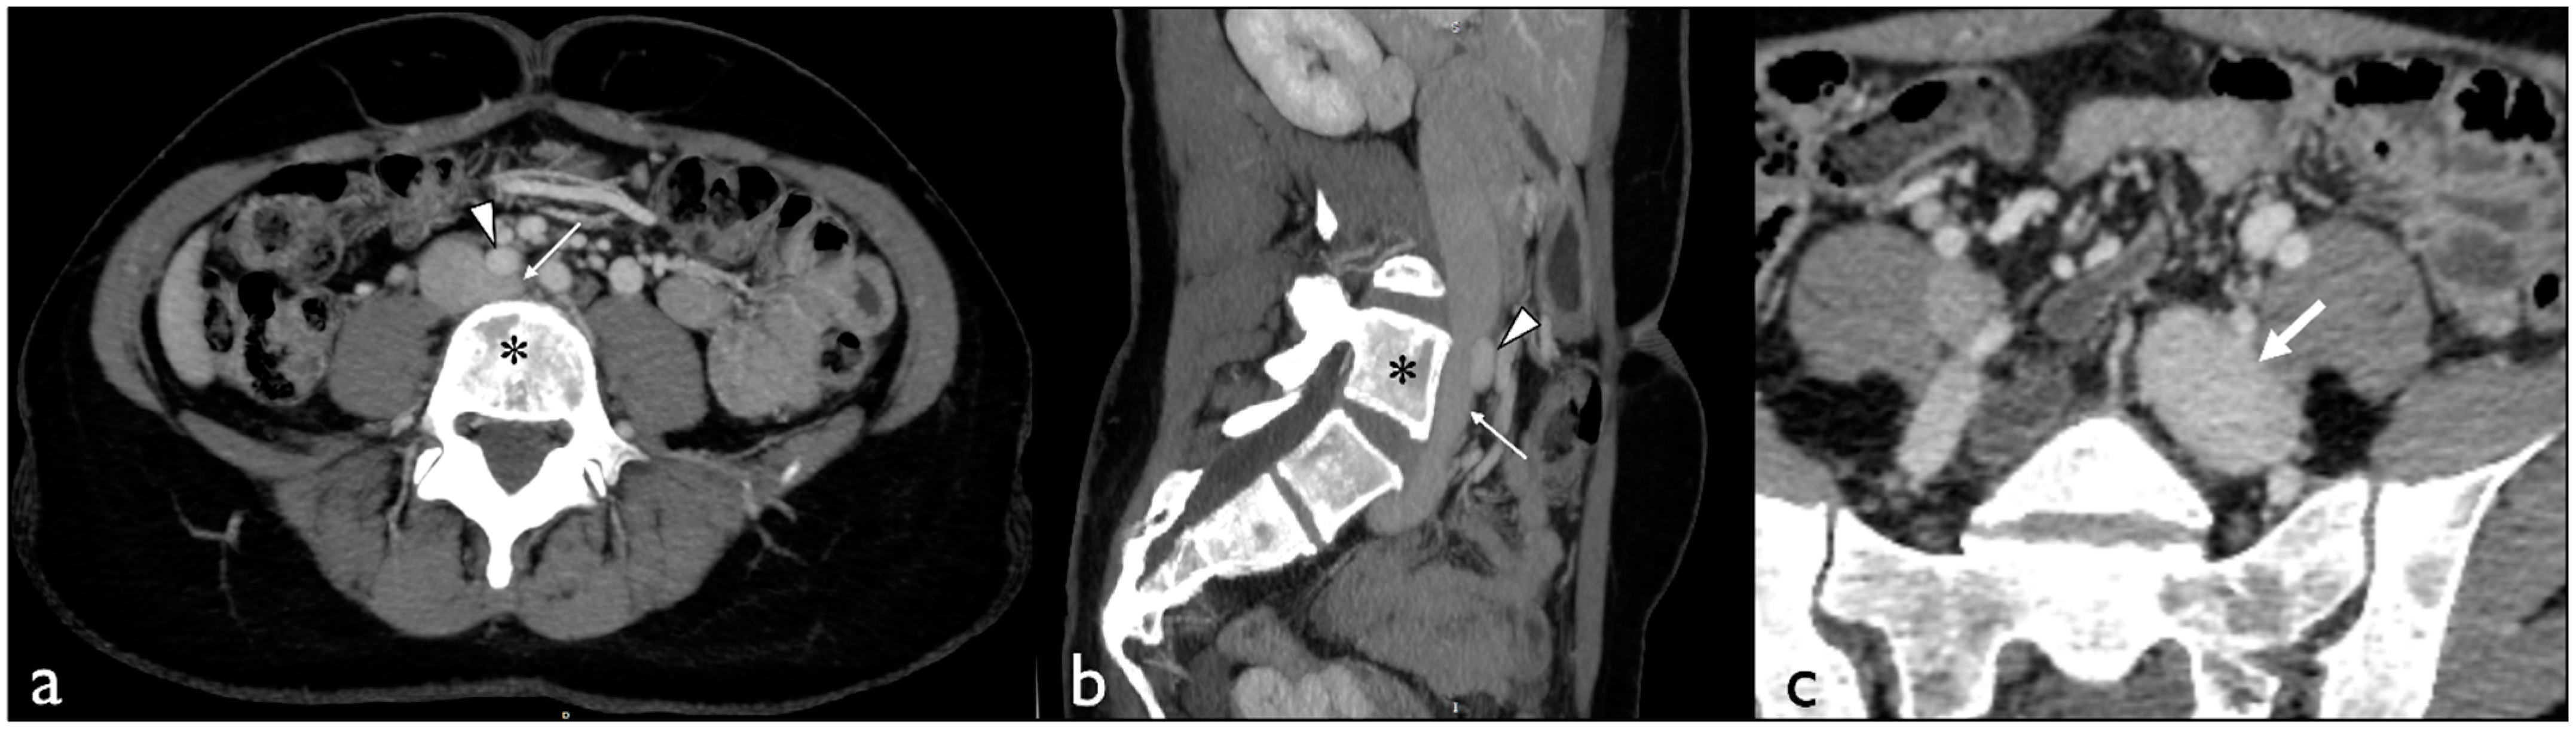

2. Case Presentation